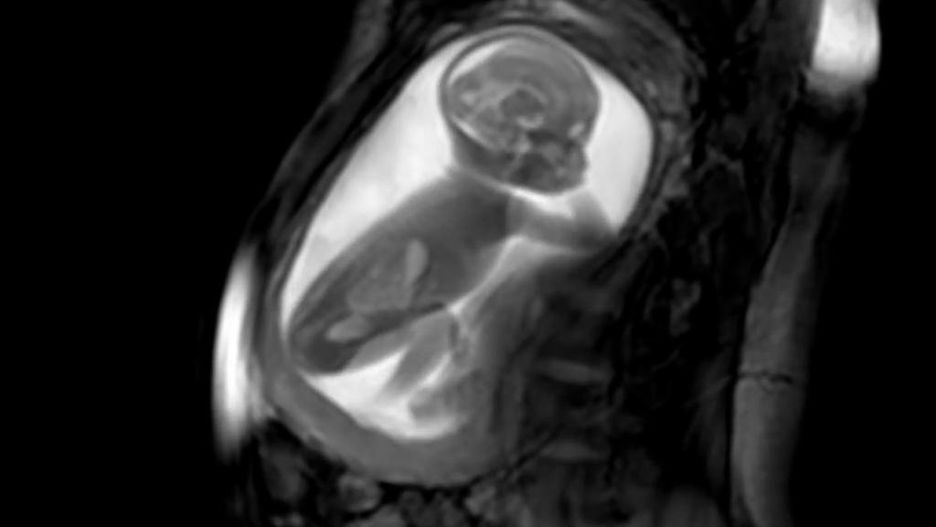

Przełom. Po raz pierwszy zobaczyli tak dokładnie serce nienarodzonego dziecka

Naukowcy stworzyli bezprecedensową technologię, dzięki której można przyjrzeć się sercu dziecka, gdy jest ono jeszcze w łonie matki.

Wszystko dzięki specjalnie zaprojektowanym modelom 3D. Ciężarne kobiety zostały przeskanowane w maszynie MRI, a następnie komputery o niezwykle dużej mocy stworzyły trójwymiarowe modele bijących serc nienarodzonych dzieci - podaje bbc.com.

Technologia pomoże w walce z wadami serca. Zespół lekarzy zrzeszonych w fundacji King's College London and Guy's and St Thomas's twierdzi, że nowa technika badań poprawi opiekę nad dziećmi z wrodzoną wadą serca. Dzięki niej możliwe będzie szybkie wykrycie oraz wdrożenie planu leczenia

Naukowcy twierdzą, że ich technologia może być bardzo łatwo zastosowana w codziennych szpitalnych zabiegach.